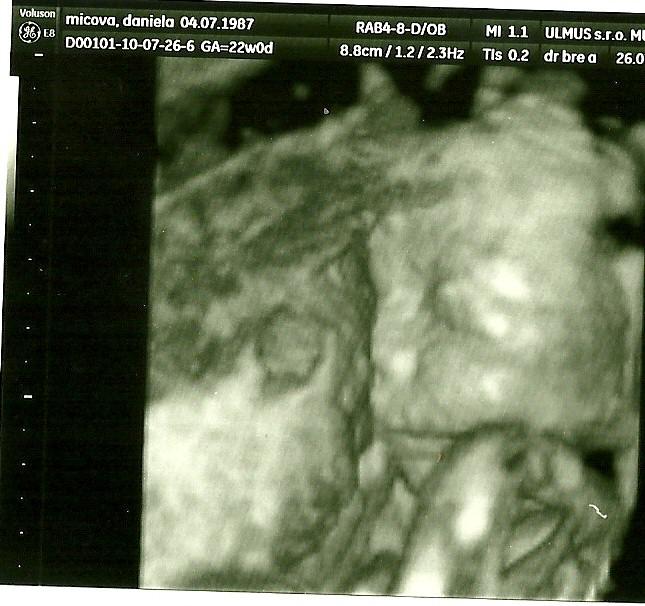

juchuu uz som doma.Super stuplik rastie ako z vody a aky je uz veliky:Daj rucicky,nozicky paraada :D zevraj bude mudry/a,lebo ma velku hlavku chichi :D:Daka som rada ze som ho zase videla 🙂

zajtra ideme na sono .... 🙂